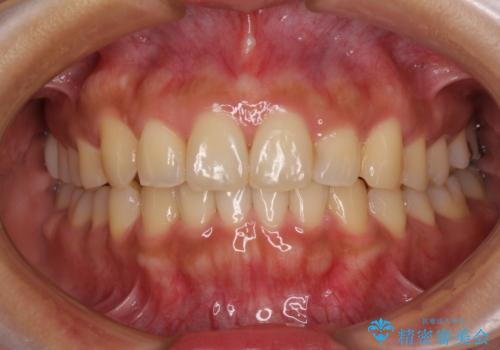

【モニター】歯列が狭くデコボコが気になる 急速拡大装置を用いたインビザライン矯正

矯正治療後には土台のままとなっている歯をセラミッククラウンにて補綴治療を行うこととしました。

上下の骨幅を改善したことで、スムーズに歯列矯正を行うことができました。

土台のまま放置されていた歯は土台の状態で咬み合っていましたが、急速拡大を行った際に咬み合わせが著しく挙上されたため、その際に土台を大きくすることで咬み合う歯との距離を確保しました。